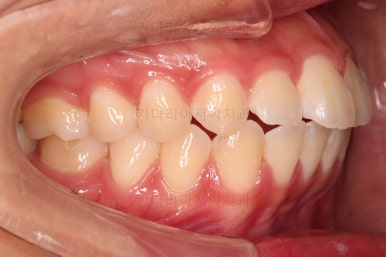

1. 초진 시 입안의 모습 평가

부산연산역치아교정 키다리아저씨치과에 처음 내원했을 당시의 입안의 모습이비다.

앞니 약간, 어금니쪽 약간 삐뚤어진 것, 그리고 위아래 앞니가 약간 뻗쳐 보이는 양상 이외에는 매우 가지런해 보여서 교정치료를 굳이 왜 하시려고 하지? 라고 생각될 정도의 치열 상태였습니다.